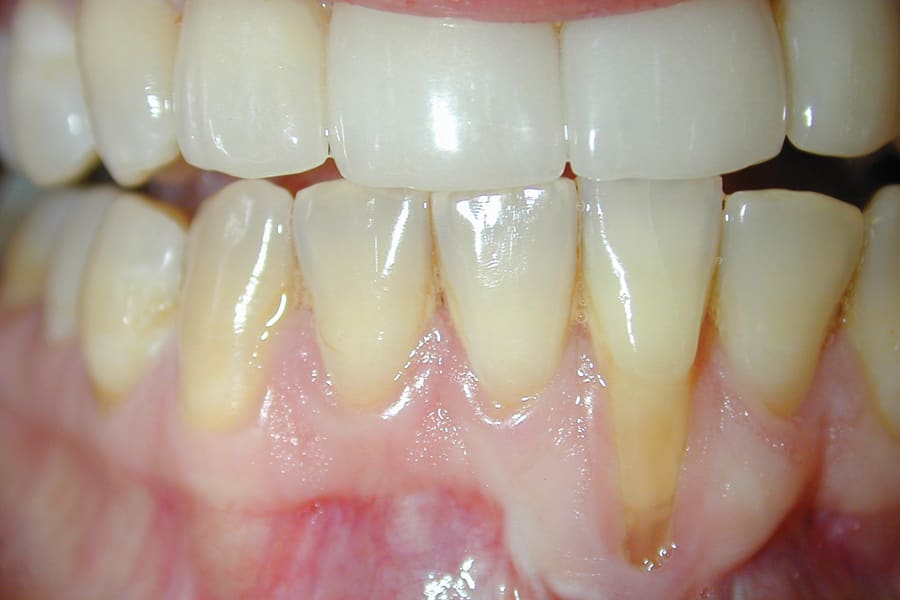

There are, however, some unfavorable long-term ramifications of this design. Due to the nature of stainless steel, which has memory and over time will partially return to its original shape, these twisted lingual retainers may "unwind" or uncoil and exert unintended forces on the teeth to which they are bonded (Figure 5 and Figure 6, Figure 8 through Figure 11, Figure 14 through Figure 16). This leads to excessive labial or lingual root torquing movements, often resulting in highly undesirable recessions, dehiscences, and fenestrations. Because it may take years for this occurrence to manifest, the orthodontist (who usually places the retainer) is typically both unaware of the situation, as he or she does not customarily follow patients for such long-term periods, and free of blame. The periodontal implications of this outcome can be highly detrimental, as seen in the cases presented herein.

A second option is to use corrective orthodontic therapy in the form of fixed appliance application to torque the root back into the correct position (Figure 5 through Figure 7). This requires full-sized archwire insertion into a precision edgewise bracket (Figure 7). This can be a time-consuming undertaking, as the step-up through various archwires until fully engaging a full-sized wire will take a few months. Nevertheless, significant corrective changes often can be observed, as the tooth's investing structures often spontaneously remodel, at least partially, in response to the corrected tooth position (Figure 5 and Figure 7, Figure 11 and Figure 13).

Although spontaneous improvement of the investing tissues is often observed through orthodontic correction (Figure 7 and Figure 13),5 additional corrective action is frequently indicated afterwards, particularly when cosmetics are to be considered. A recession defect case is depicted in Figure 17 through Figure 26 in which corrective action was necessary and accomplished through aligner therapy followed by connective tissue grafting.6 It should be noted that although this corrective scheme may successfully achieve an acceptable cosmetic and functional result, it is not likely a regenerative outcome in the sense that a previously dehisced root surface typically will not attain ligamentous insertion into freshly laid cementum. A long junctional epithelium or connective tissue attachment at best is the more likely outcome. Consequently, a preventive approach initially would be more desirable.